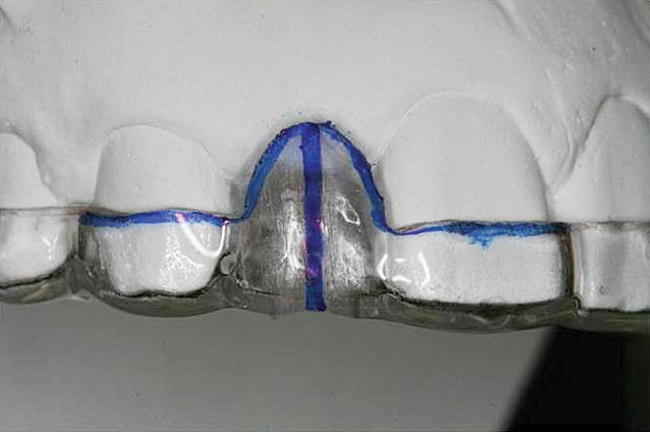

Figure 13   Exploiting study casts for planning single-tooth implant placement and restoration: Mounted study casts permit an estimation of available bone volume (Fig 13); measure the bound edentulous space inter-tooth dimensions (Fig 14); measure the available inter-arch dimension (restorative space) (Fig 15); and evaluate alveolar ridge/tooth relationships (distance from zenith represented by plastic stent to ridge crest) (Fig 16).

Figure 13

Figure 14   Exploiting study casts for planning single-tooth implant placement and restoration: Mounted study casts permit an estimation of available bone volume (Fig 13); measure the bound edentulous space inter-tooth dimensions (Fig 14); measure the available inter-arch dimension (restorative space) (Fig 15); and evaluate alveolar ridge/tooth relationships (distance from zenith represented by plastic stent to ridge crest) (Fig 16).

Figure 14

Figure 15  Exploiting study casts for planning single-tooth implant placement and restoration: Mounted study casts permit an estimation of available bone volume (Fig 13); measure the bound edentulous space inter-tooth dimensions (Fig 14); measure the available inter-arch dimension (restorative space) (Fig 15); and evaluate alveolar ridge/tooth relationships (distance from zenith represented by plastic stent to ridge crest) (Fig 16).

Figure 15

Figure 16  Exploiting study casts for planning single-tooth implant placement and restoration: Mounted study casts permit an estimation of available bone volume (Fig 13); measure the bound edentulous space inter-tooth dimensions (Fig 14); measure the available inter-arch dimension (restorative space) (Fig 15); and evaluate alveolar ridge/tooth relationships (distance from zenith represented by plastic stent to ridge crest) (Fig 16).

Figure 16